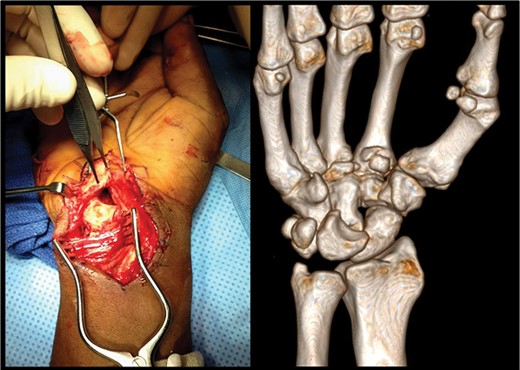

After stabilization, open reduction of the perilunate dislocation with a carpal tunnel release was performed through a combined volar and dorsal approach 12 h after presentation (Fig. 2). The lunate had no ligamentous attachments and was free floating in the distal forearm. The scapholunate and lunotriquetral ligaments were completely avulsed and irreparable. Reduction was achieved with manipulation using a joystick technique with K-wires placed into the scaphoid and lunate. K-wires were placed through the scaphocapitate, scapholunate and lunotriquetral intervals (Fig. 3). The CMC subluxations were stable when stressed under fluoroscopy, establishing the chronicity of these injuries.

Left: intraoperative image demonstrating the dislocated lunate sitting anterior to the carpal tunnel prior to operative reduction. Right: preoperative volar view of a three-dimensional CT reconstruction of a right wrist. Dislocation of the lunate from the carpus is noted.